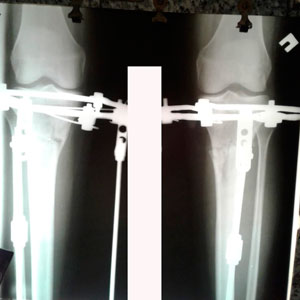

в процессе работы

image-26-06-20-10-34-2.jpg

Крутки продолжаются!

image-02-07-20-02-13-15.jpg